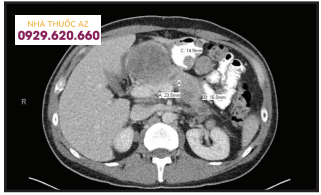

Một người đàn ông 57 tuổi đến khám với phàn nàn về chứng đau bụng vùng thượng vị sau ăn trong tháng qua cũng như giảm cân không chủ ý khoảng 5kg. Tiền sử bệnh trong quá khứ của anh ta không có gì đáng kể. Khám sức khỏe của anh ấy cho thấy khám bụng bình thường, không có đau khi sờ hoặc sờ thấy khối. Các xét nghiệm ban đầu bao gồm : Transaminase aspartate (AST) là 56 (đơn vị / L), alanin transaminase (ALT) là 65 (đơn vị / L) và phosphatase kiềm là 192 (IU / L), với bilirubin bình thường, tỷ lệ INR bình thường và số lượng tiểu cầu bình thường. Anh ta đã được khám bởi một bác sĩ chuyên khoa tiêu hóa, và một cuộc nội soi trên và nội soi đại tràng đã được lên kế hoạch để đánh giá cơn đau bụng của anh ta. Trong lúc đó, siêu âm bụng cho thấy nhiều khối lớn trong khoang phúc mạc. Sau đó, chụp cắt lớp vi tính đối chiếu vùng bụng và khung chậu cho thấy vô số khối u gieo rắc trong khoang phúc mạc, mạc treo, sau phúc mạc và phúc mạc, mô tuyến tụy cũng như các tổn thương quanh và trong dạ dày. Tổn thương nguyên phát không thể xác định được.

Chụp CT Scan bụng cho thấy phúc mạc của ổ bụng bị xâm lấn dọc theo vách sau dạ dày và một nốt 1,5 cm trên mặt sau của hang vị dạ dày.